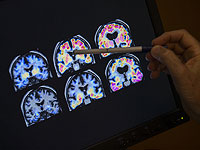

Почему мозги разных людей видят мир одинаково: открытие израильских нейробиологов

Ученые из Университета Райхмана и Института Вейцмана выяснили, почему люди с различной структурой мозга воспринимают окружающий мир похожим образом.

Исследователи под руководством Офера Липмана изучили данные пациентов с эпилепсией, которым для лечения были имплантированы электроды в мозг. Это позволило сравнить активность нейронов в реальном времени, пока люди смотрели на одинаковые изображения. Работа опубликована в журнале Nature Communications.